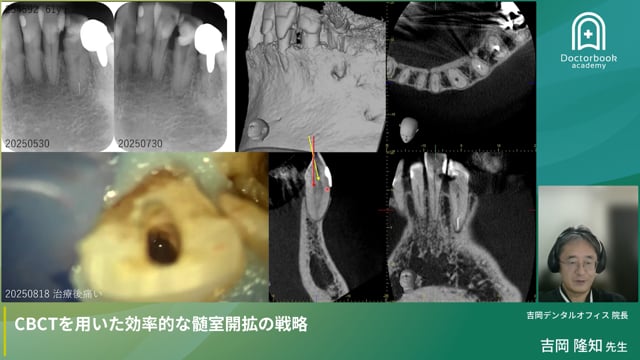

症例では、CTを用いた石灰化根管の攻略、超音波+スティッキー材による破折器具除去、ストリッピング穿孔の封鎖、極小アクセス失敗例の再設計を提示します。高解像度CTと適切なバー選択により、安全で効率的な根管治療を実現する戦略が学べます。

・CTと超音波を軸にした石灰化根管の攻略、破折器具除去、穿孔封鎖の具体的プロトコル。

プレミアムCBCTを用いた効率的な髄室開拡の戦略根管治療のアクセス設計を再考します。小さすぎる開拡のリスク、CT活用、破折器具除去や穿孔封鎖の実際を症例で学べます。再生する